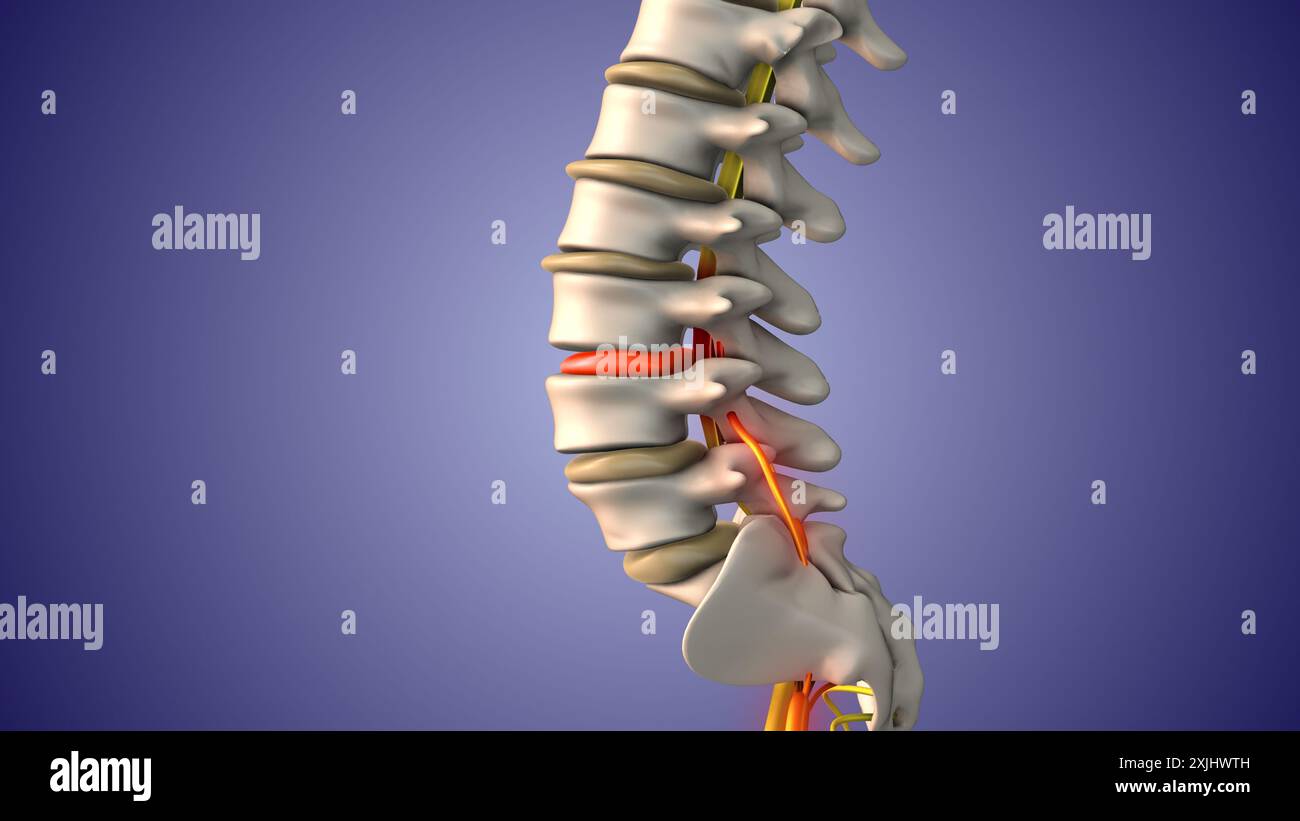

Ischiasnervenschmerz durch Bandscheibenvorfall Stockfotohttps://www.alamy.de/image-license-details/?v=1https://www.alamy.de/ischiasnervenschmerz-durch-bandscheibenvorfall-image613820161.html

Ischiasnervenschmerz durch Bandscheibenvorfall Stockfotohttps://www.alamy.de/image-license-details/?v=1https://www.alamy.de/ischiasnervenschmerz-durch-bandscheibenvorfall-image613820161.htmlRF2XJHWTH–Ischiasnervenschmerz durch Bandscheibenvorfall